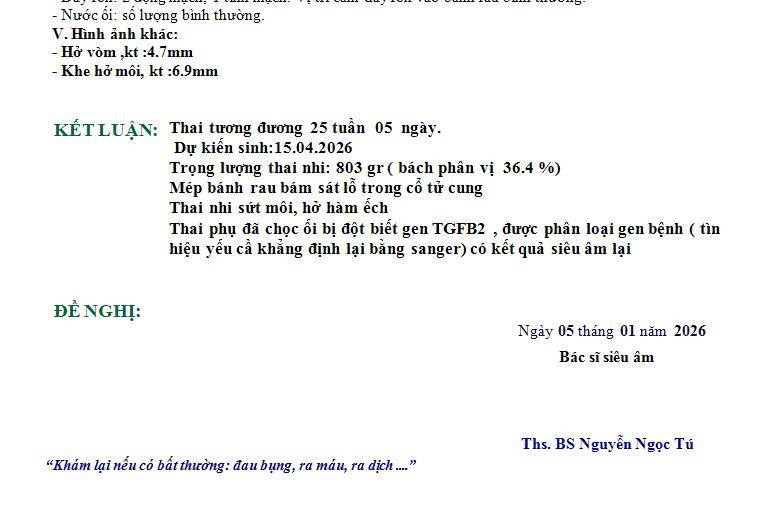

Thai nghi ngờ sứt môi, hở hàm ếch.

Khi vào phòng siêu âm, bác sĩ Tú không vội nói gì. Bác sĩ xem lại toàn bộ hồ sơ, xem kỹ hình ảnh, hỏi lại thời điểm làm siêu âm trước. Sau đó bác sĩ mới quay sang chị H. và nhẹ nhàng nói:

“Mình cần hiểu rõ sứt môi hở hàm ếch thực sự là gì, và trường hợp của em đang ở mức nào.”